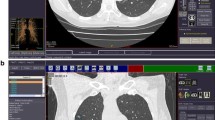

The CAD system (Siemens Medical Solutions, Erlangen, Germany; Siemens Corporate Research, Princeton, NJ) is a knowledge-based automatic lung nodule detection prototype comprising multiple “expert processing modules” to detect nodules with or without pleural or vascular attachment. Solitary nodules are recognized by an adaptive local histogram-based threshold-aided segmentation algorithm. After the structure is classified within a volume of interest (VOI), the chest wall is recognized and automatically removed if included in the VOI. After this, the potential nodule is extracted using a 3D-template method. Principle component analysis and classification tools ensure the segmentation of nodules in the presence of vessel attachment and the exclusion of structures recognized as non-nodules. An automatic bronchus recognition system allows for reduction of false-positive ratings simulated by bronchial wall thickening. The CAD segmentation algorithm has been described previously [15]. The CAD system offers a percentual confidence level for diagnosis of each lung nodule that was used for subsequent statistical analysis. Additionally, each nodule diameter is displayed on the output screen (Fig. 1). CAD image data evaluation was performed after evaluation by the two study readers.

Surface of CAD showing a results section containing position data, confidence level score and size measurements. The full axial slice display shows recognized structures marked by arrows (here nodule confirmed by the reference standard in right posterior upper lobe, arrow). The 3D display at the top left shows in this case a nodule with vascular attachment